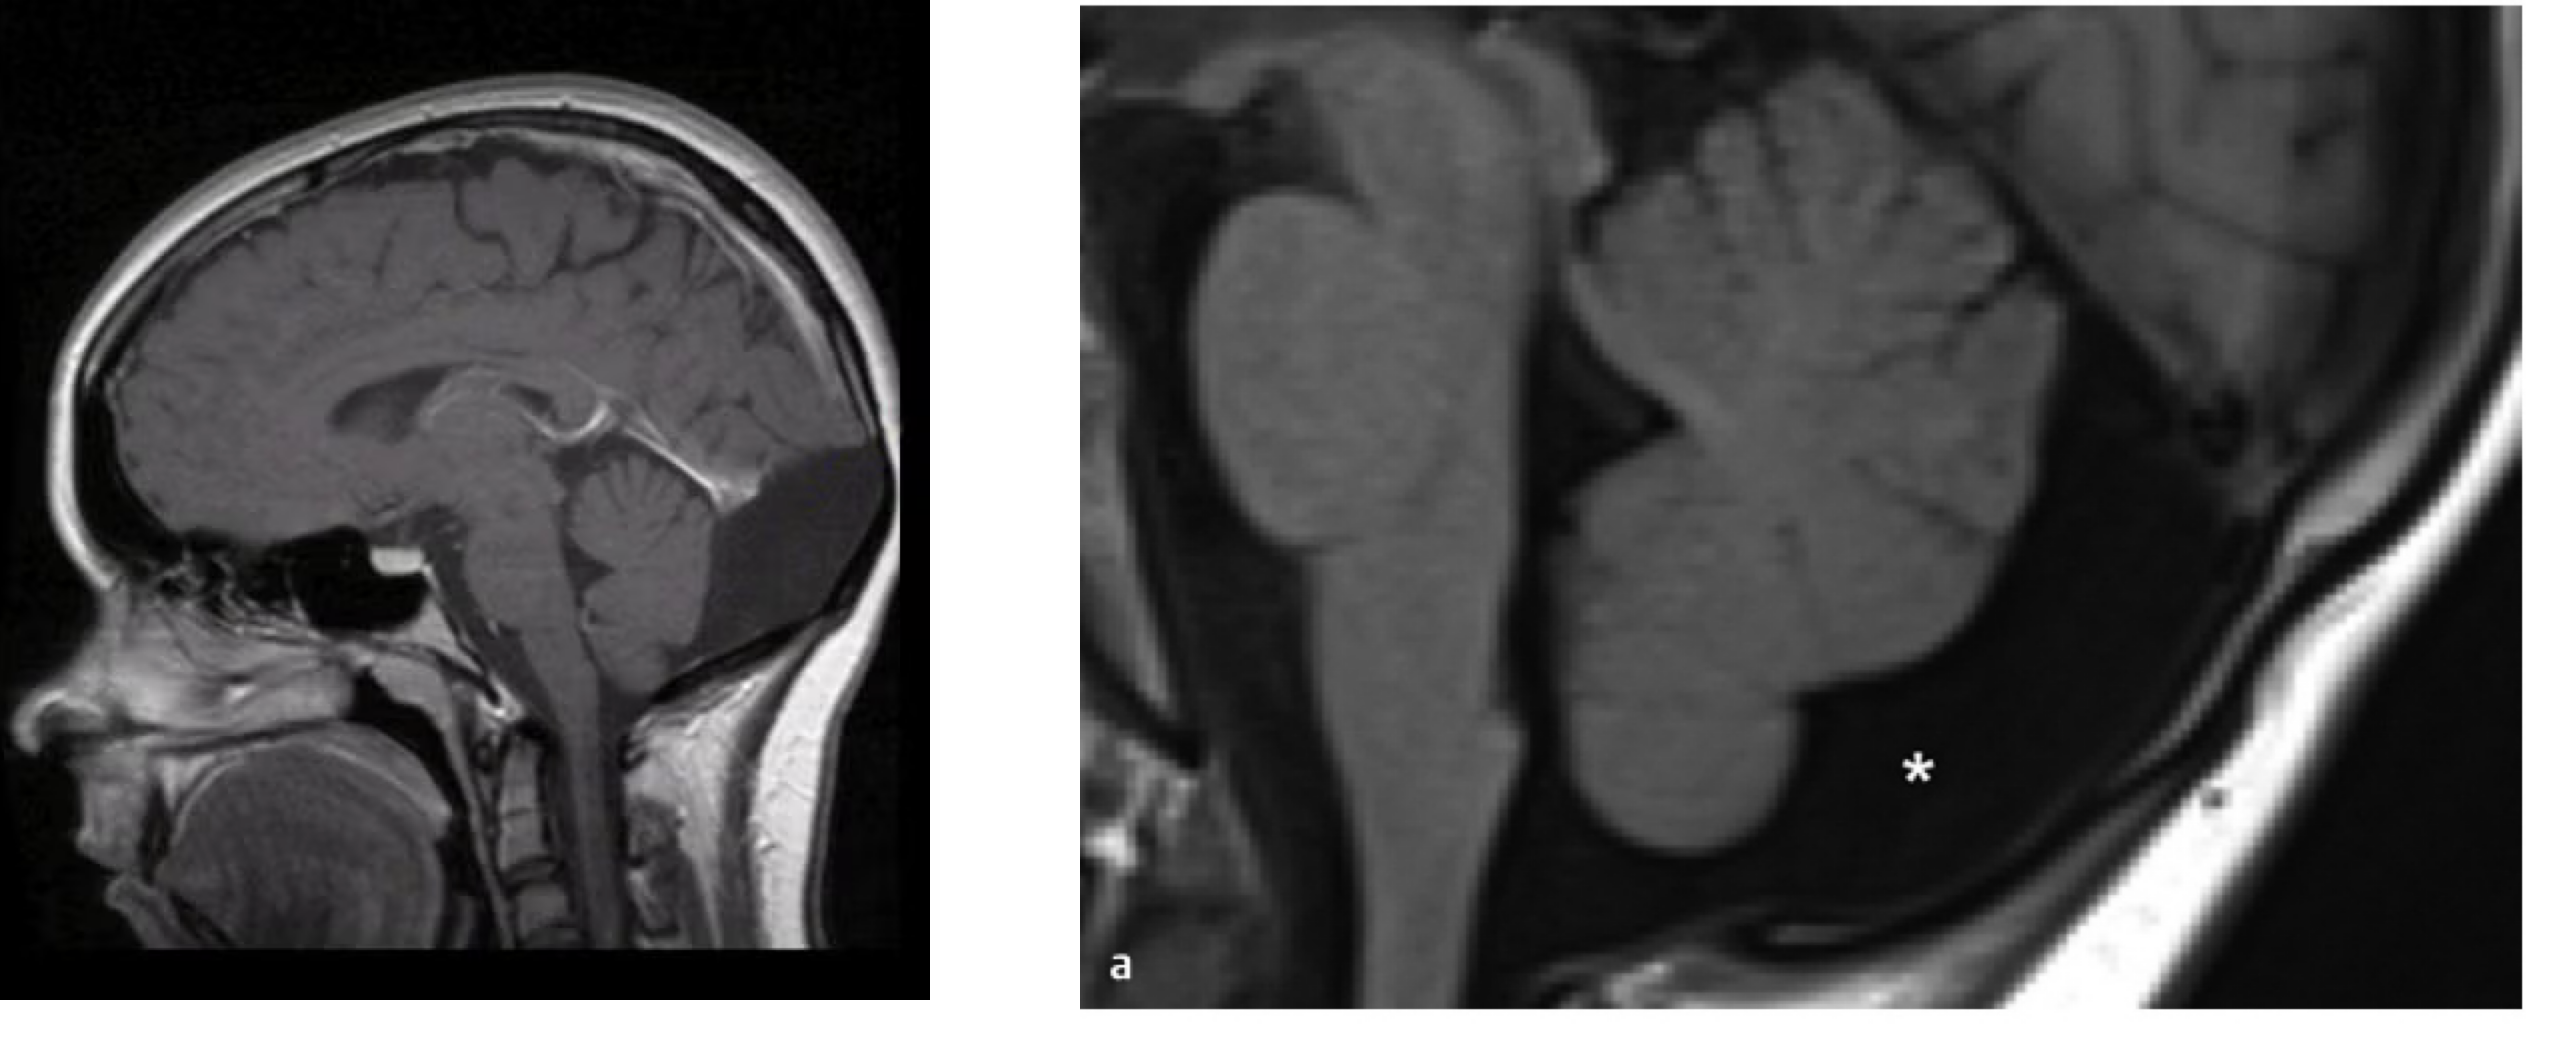

Chiari malformation

정의: 후두와(Posterior cranial fossa)의 크기 또는 형태 이상으로 인해, 소뇌 구조(특히 편도)가 foramen magnum 아래로 전위(herniation)되는 질환

Type I: cerebellar tonsils 이 foramen magnum 아래 ≥5 mm 하강.

Type II: (Arnold-Chiari malformation): 소뇌 벌레(vermis), 제4뇌실, 연수가 foramen magnum 아래로 하강, 거의 항상 myelomeningocele 동반

Dandy-walker malformation

정의: 발생학적 이상으로 인해 cerebellar vermis의 부분/완전 결손 및 superior rotatio과 4th ventricle의 cystic dilatation, 확대된 후두와가 특징인 복합 기형. CSF 순환장애 및 수두증 흔히 동반

posterior fossa arachnoid cyst (좌): 후두와의 낭성 병변, normal cerebellar vermis, 4th ventricle과의 연결 없음

mega cisterna magna (우): 후두와 크기 정상, 소뇌/뇌실 정상, cisterna magna 직경 >10mm